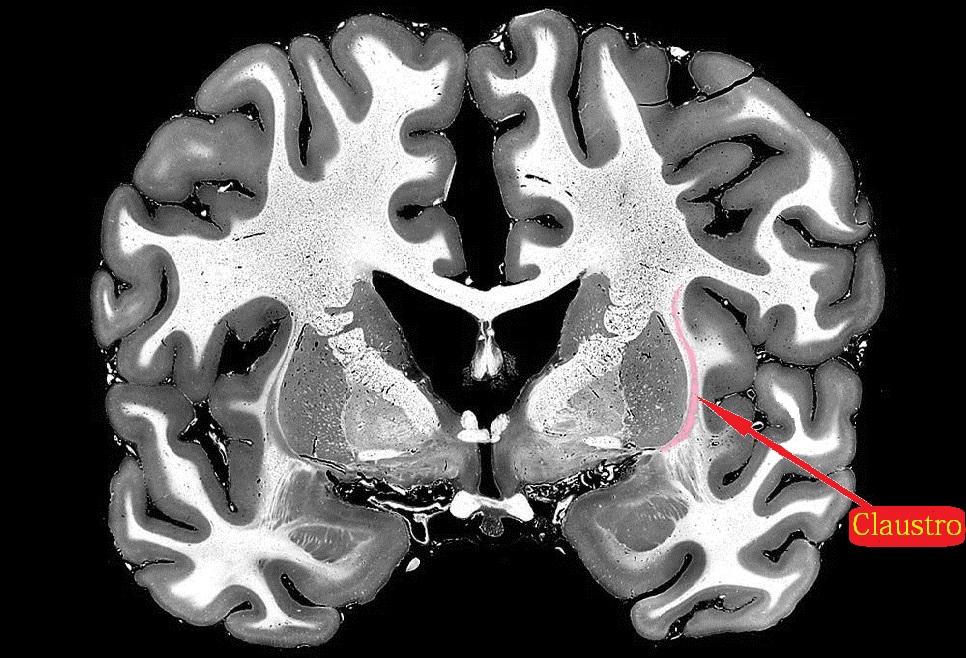

El trabajo liderado por Christof Koch, del Allen Institute for Brain Science, mostró cómo el equipo científico fue capaz de rastrear tres neuronas a través de una capa de células extremadamente pequeña y delgada llamada claustrum (claustro); se sospecha que esta región cerebral actúa como comando de la consciencia humana.

El claustrum es una delgada capa de materia gris que aparenta ser la estructura más conectada de todo el cerebro; una pequeña región que se oculta entre la superficie interna del neocórtex en el centro del cerebro, y que se comunica con casi todas las regiones de la corteza para lograr las funciones cognitivas superiores (visión, audición, lenguaje, etc.).